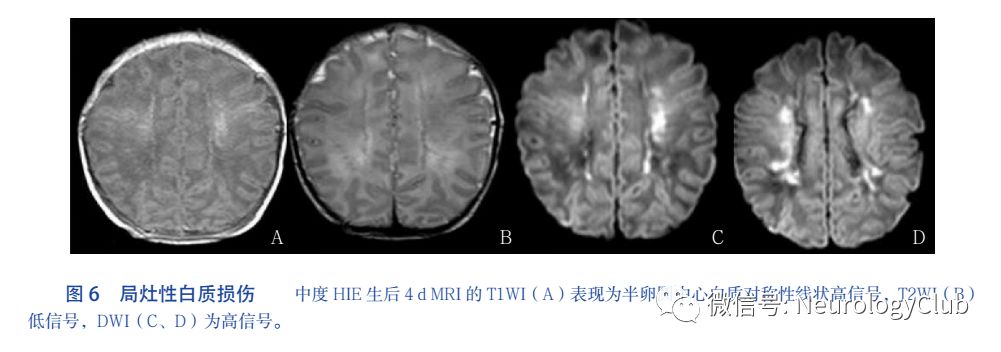

3.3 局灶-多灶性微小性白质损伤

白质损伤主要分布在脑室周围及半卵圆中心区白质,病变特征为点状,数量不等,有时呈线状或成簇存在早期T1WI为高信号,T2WI为低信号或等信号,DWI为高信号。见图6。SWI多数不表现信号的缺失(低信号),提示改变的主要原因是胶质细胞增生多灶性损伤病灶周围的白质可表现明显的T2WI高信号。也有放射诊断专家认为局灶-多灶性微小性白质损伤属于分水岭样损伤,不过最近研究表明它是足月新生儿HIE很常见的一种损伤,可能与胎盘炎症反应程度有关,但尚不清楚是否是由于炎症反应导致胎盘功能不全、进而发生胎儿缺氧缺血和新生儿窒息所致。此外该类型多发生在早期足月新生儿,也是早产儿常见的脑白质损伤类型。因此,我们把它单独作为一种类型。